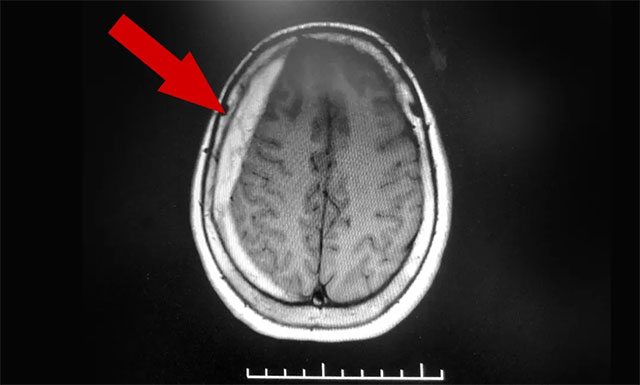

▲ 患者右側(cè)額顳部顱骨內(nèi)板下方呈新月形高密度影

侯增欣主任結(jié)合患者病史陳述及影像學(xué)檢查后診斷為——亞急性硬膜下血腫。當(dāng)被家人送回上海藍(lán)十字腦科醫(yī)院并收治于神經(jīng)外科6A病區(qū)后不久,金阿婆便開始出現(xiàn)意識(shí)模糊等危重癥狀況。侯增欣主任團(tuán)隊(duì)緊急討論評(píng)估后認(rèn)為,患者血腫面積較大,且癥狀不斷加重,需立即進(jìn)行手術(shù)治療。